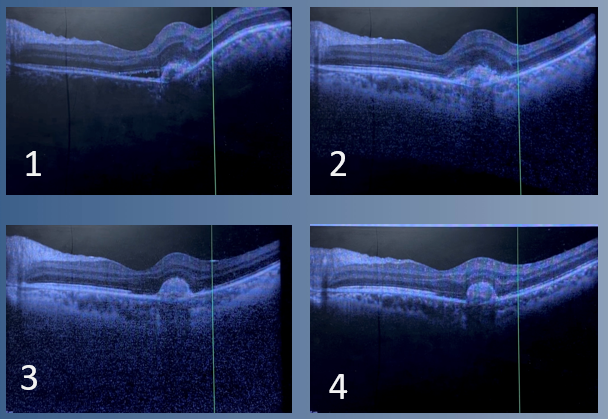

File:OCT macula in TAGU.png

From July to October, 1,2,3,4

Developing drusenoid deposit parafoveally + SRF Enlarging + SRF Drusenoid deposit enlarged, no SRF, some RPE drop out Stable. Poor foveal contour